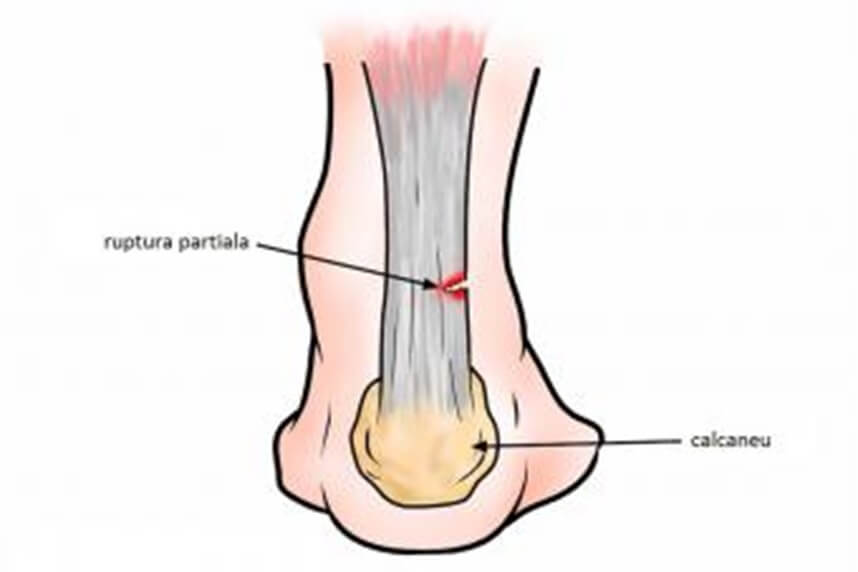

Ruptura tendonului lui ahile

Tendonul lui Ahile este cel mai mare si cel mai robust tendon din corpul uman.

Stresul repetitiv la sportivi sau simpla imbatranire in cazul persoanelor inactive pot duce la variatii in structura acestui tendon. Acest lucru poate duce la rupturi partiale sau chiar complete ale tendonului. Aceste afectiuni de multe ori rezulta din tendinita cronica nerecunoscuta sau gresit inteleasa. Ea afecteaza mai ales alergatorii, fotbalistii si jucatorii de tenis. Se crede ca ar fi rezultatul unei contractii bruste.

Atletii afirma deseori ca au avut senzatia primirii unei lovituri din partea adversarului. Ruptura genereaza o deteriorare functionala imediata, impiedicand orice fel de miscare.

Diagnosticul se bazeza in principal pe prezentarea clinica: uneori exista un gol evident la locul rupturii. Diagnosticul suspectat este de obicei confirmat de o ecografie care arata clar intreruperea fibrelor tendonului si care ne permite sa distingem intre rupturile partiale si cele totale.

In aceste cazuri, intotdeauna este necesara inverventia chirurgicala.

Recuperarea este de lunga durata. Dupa o anumita perioada de imobilizare post¬-chirugicala, incarcarea tendonului se face progesiv, mersul complet fiind recuperat in cateva luni.